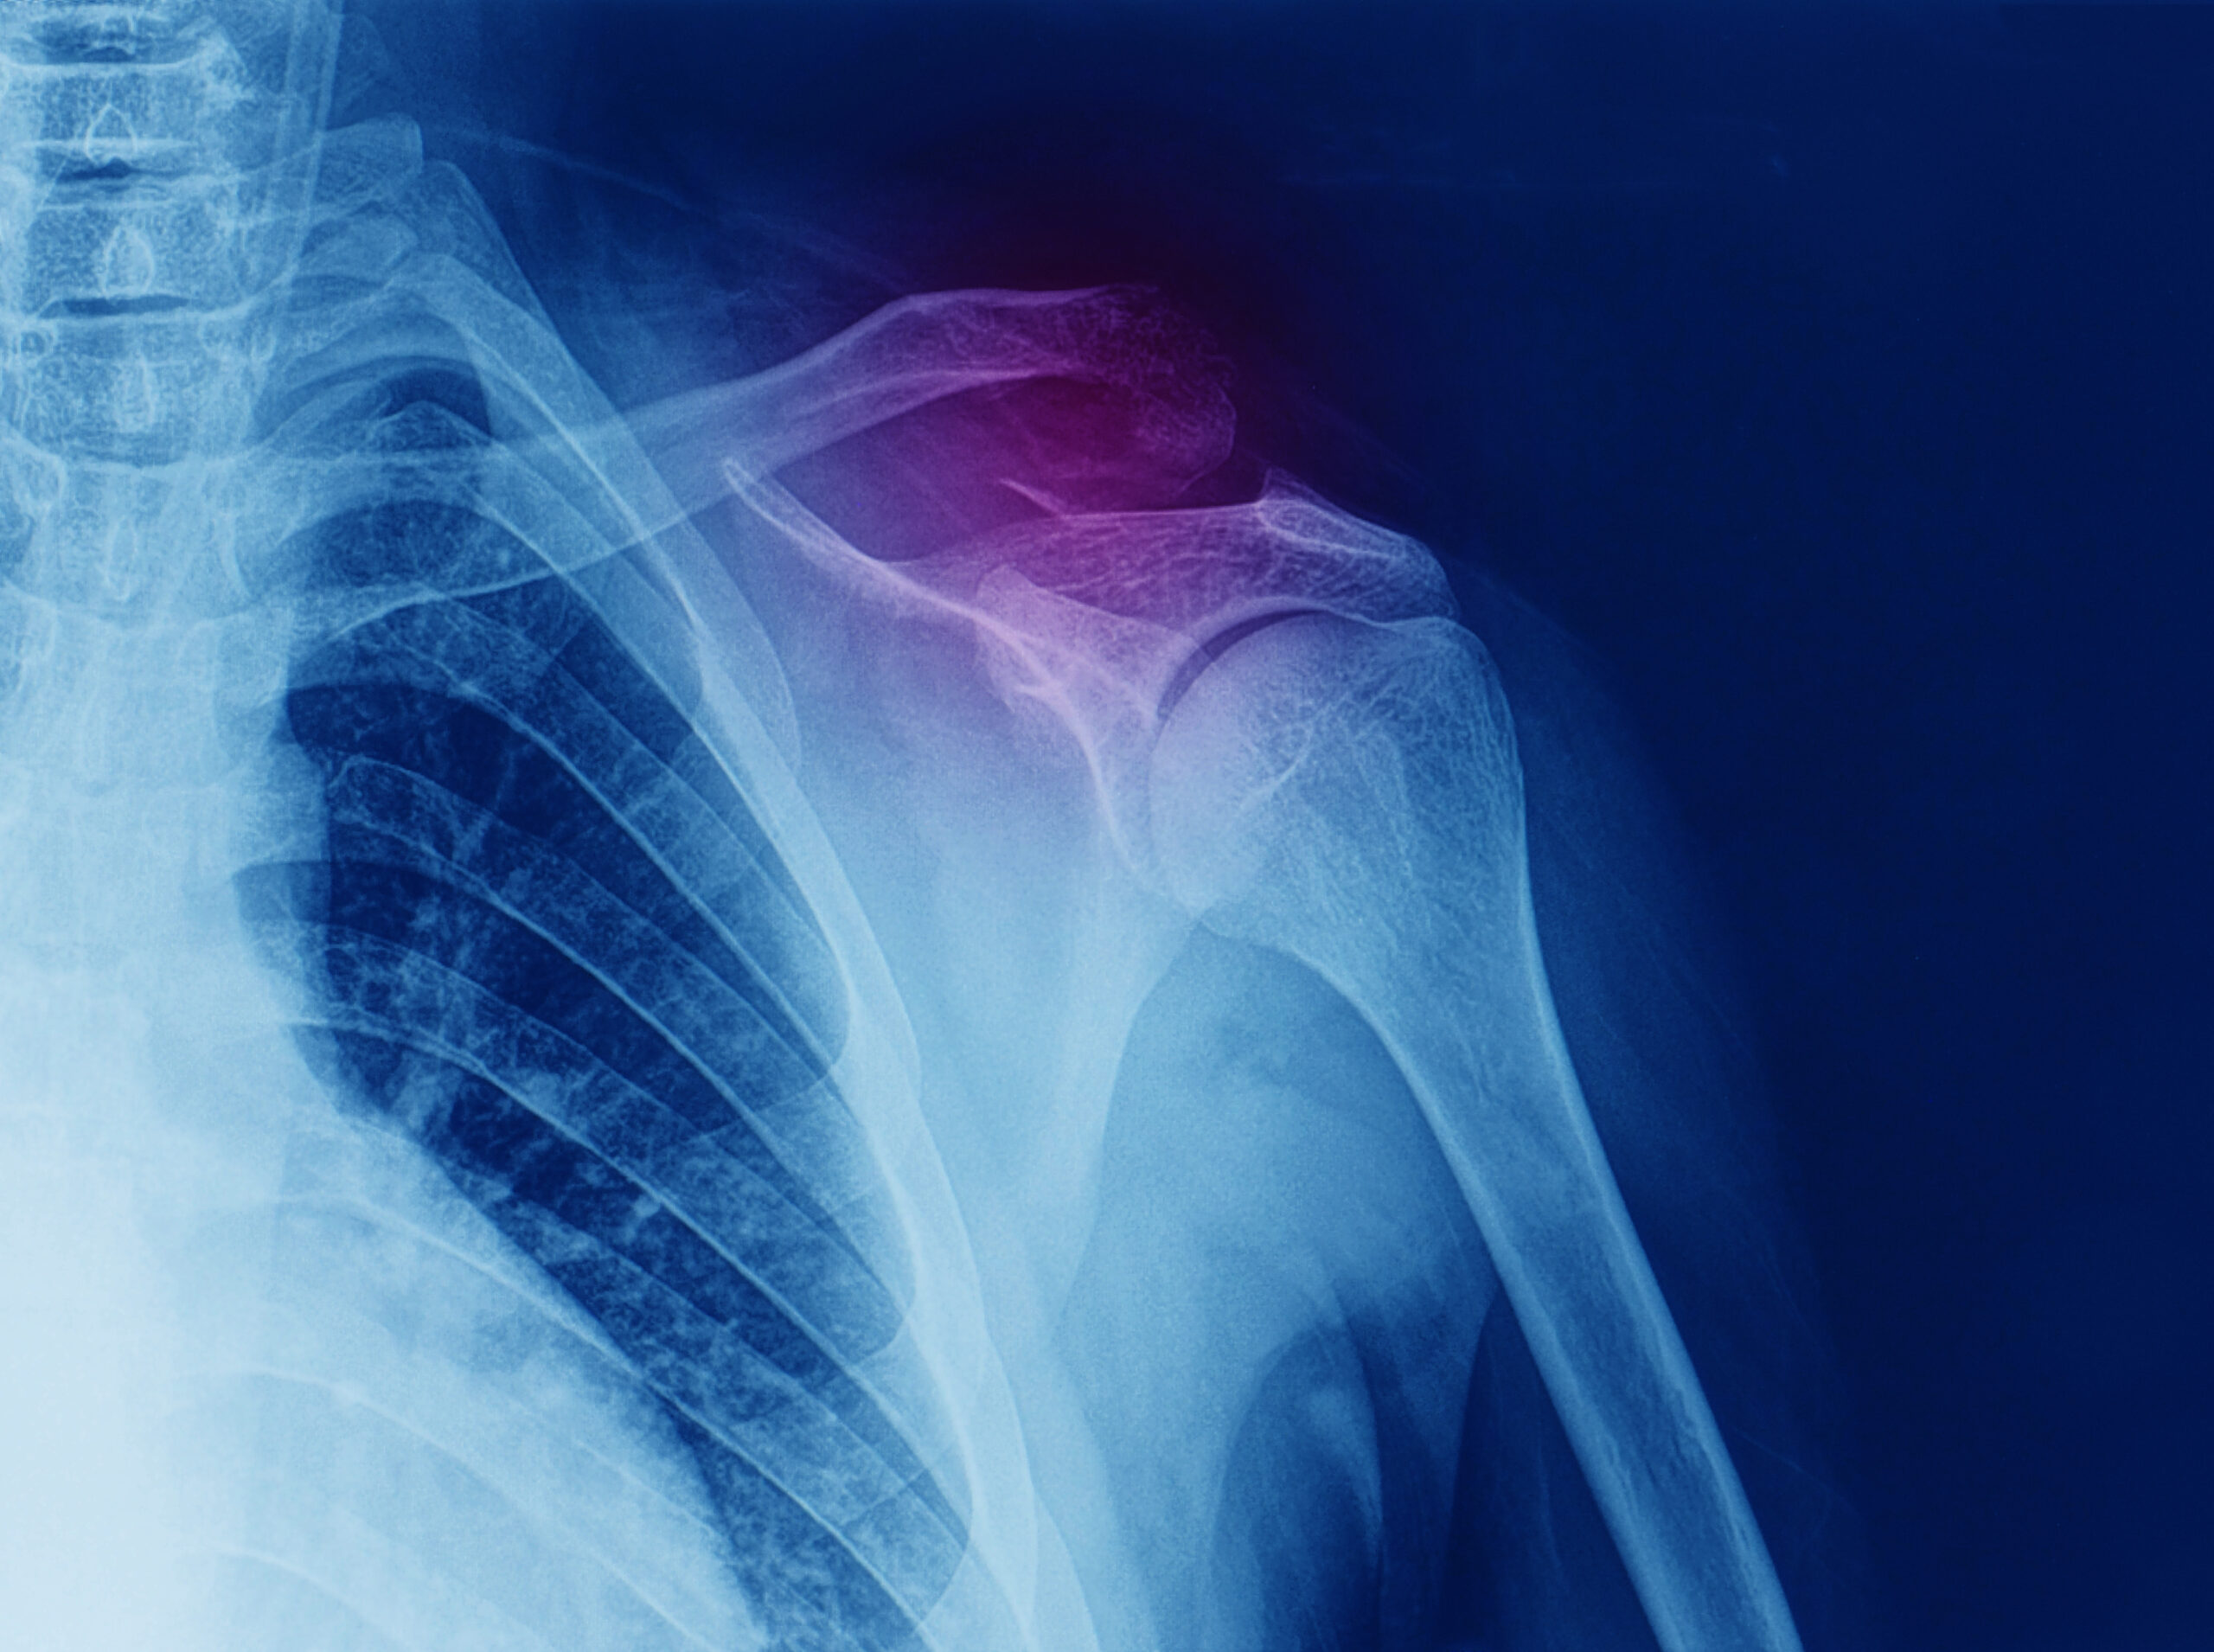

با دکتر دانشیار عطاء جان، متخصص ارتوپدی و تروما‌تولوژی در ارتباط باشید تا پرسش‌های خود را برطرف کرده و یا نوبت دریافت کنید.